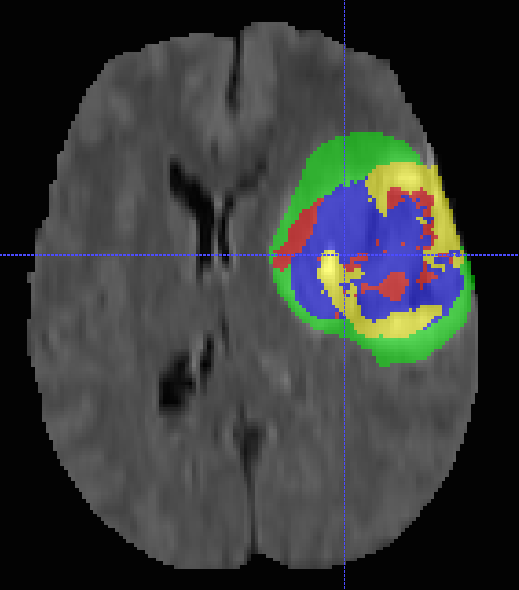

In this section, we consider multi-modal brain-tumor segmentation in MRI brain scans an example of which is depicted in Fig. 16. Segmentation quality critically depends on the amount of training data and only highly-trained experts can provide it. We use the BRATS dataset where T, T, FLAIR, and post-Gadolinium T MR images are available for each of subjects [69]. We use standard filters such as Gaussian, gradient filter, tensor, Laplacian of Gaussian and Hessian with different parameters to compute the feature vectors we feed to the Boosted Trees. Notice that we use different features compared to EM images that demonstrates that our method can be applied in different applications.

Multi-class segmentation To test our multi-class approach, we use the full label set of the BRATS competition: healthy tissue (label ), necrotic center (), edema (), non-enhancing gross abnormalities (), and enhancing tumor core (). Fig. 18 shows a ground truth example for one slice in one of the volumes. Different classes are indicated in different colors. Note that the ground truth is highly unbalanced: we have samples of healthy tissue, of edema, of enhancing tumor core, of necrotic center and of non-enhancing gross abnormalities in the full training dataset. We use the evaluation protocol of the BRATS competition [69] to analyse our results. This involves evaluating how well we segment complete tumors (classes , , , and ), core tumors (classes , , and ), and enhancing tumors (class only).